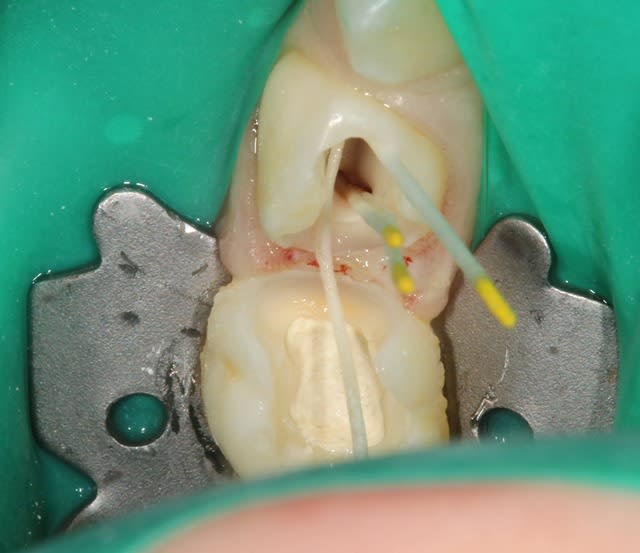

Voilà, premier cas (il y a un début à tout) où j'ai posé la digue pour un soin de A à Z sur un môme de 8ans pour soigner sa 55.

Oui, c'est bien une fistule, quand il a ouvert la bouche en arrivant, je me suis dit : bon ben je suis parti pour la pulpectomie, en ouvrant tous les canaux étaient bien vivants, du coup je me suis contenté de la pulpo.

J'ai percé en fin de séance, pas grand chose n'est sorti. J'ai pas la radio dispo pour vous la montrer, mais j'ai rien remarqué de particulier que ce soit sur la 55 ou sur la dent définitive.